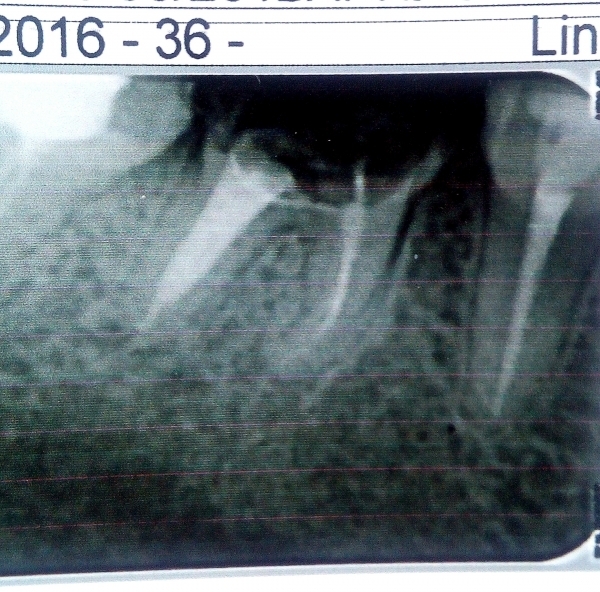

Хорошо, что Вы предоставили снимок, но плохо, что нет снимков до вмешательства. Для точного ответа нужен снимок до распломбировки. По снимку четко видно, что на переднем корне киста, вполне возможно она обострилась после того, как ее побеспокоили.

Вопрос в другом. Этот зуб однозначно подлежит удалению. И это никак не связано с каналами. Дело в том, что у зуба проблема с бифуркацией, она истончена, и в кости в данной области намечается разрежение, которое однозначно проявится после протезирования и принесет проблемы. То есть по снимку можно сказать, что каналы сделаны старательно. Но стратегическое решение принято ошибочное — вопрос об удалении зуба надо было поднимать до распломбировки из-за кисты на верхушке переднего корня, и самое главное — из-за проблем в бифуркации.